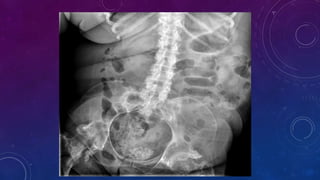

SPOT 3 ORGANS

WITH

CALCIFICATIONS

Gall stone

Calcific pancreatiits

Penile calcification